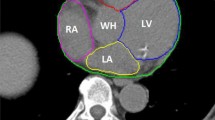

The aim of this study is to evaluate a regional deformable model based on a deep unsupervised learning model for automatic contour propagation in breast cone-beam computed tomography–guided adaptive radiation therapy. A deep unsupervised learning model was introduced to map breast’s tumor bed, clinical target volume, heart, left lung, right lung, and spinal cord from planning computed tomography to cone-beam CT. To improve the traditional image registration method’s performance, we used a regional deformable framework based on the narrow-band mapping, which can mitigate the effect of the image artifacts on the cone-beam CT. We retrospectively selected 373 anonymized cone-beam CT volumes from 111 patients with breast cancer. The cone-beam CTs are divided into three sets. 311 / 20 / 42 cone-beam CT images were used for training, validating, and testing. The manual contour was used as reference for the testing set. We compared the results between the reference and the model prediction for evaluating the performance. The mean Dice between manual reference segmentations and the model predicted segmentations for breast tumor bed, clinical target volume, heart, left lung, right lung, and spinal cord were 0.78 ± 0.09, 0.90 ± 0.03, 0.88 ± 0.04, 0.94 ± 0.03, 0.95 ± 0.02, and 0.77 ± 0.07, respectively. The results demonstrated a good agreement between the reference and the proposed contours. The proposed deep learning–based regional deformable model technique can automatically propagate contours for breast cancer adaptive radiotherapy. Deep learning in contour propagation was promising, but further investigation was warranted.